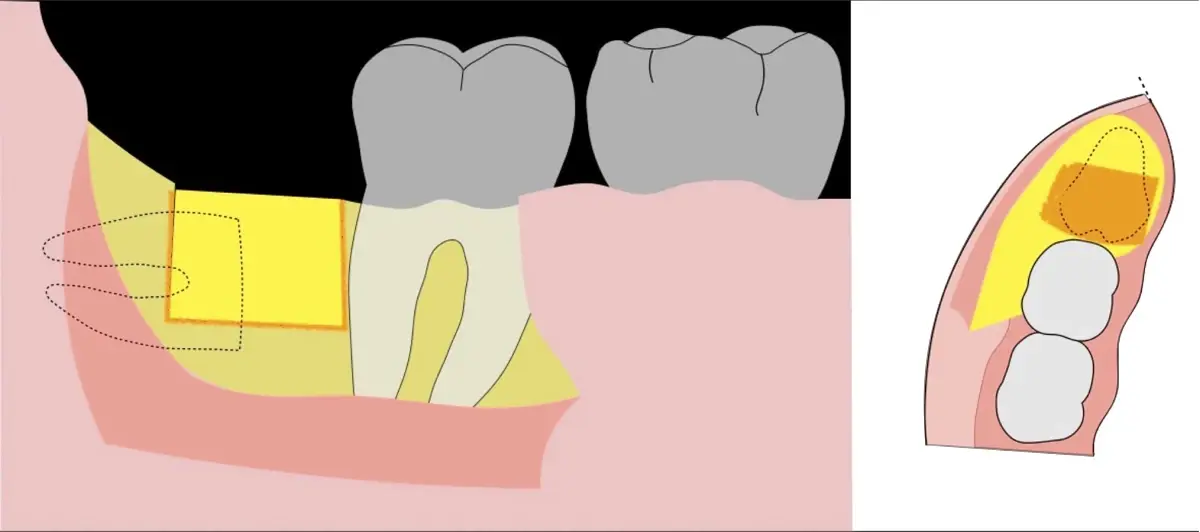

Figura 5. Fractura y eliminación oclusal del fragmento óseo de la porción coronal oclusal.

Figura 6. Demarcación y fractura de la zona de osteotomía a nivel vestibular con inserto aserrado recto y/o angulado.